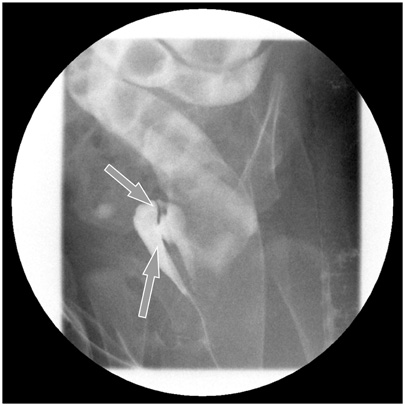

A 2-month-old female infant presented to our hospital with a 1-month history of stool passing through the vagina. She was born at 36 weeks' gestation weighing 1.875 kg and was the second infant of a twin. She had a ventricular septal defect that closed spontaneously at 1 month of age. Initially, she was diagnosed with a rectovaginal fistula. Despite conservative therapy, including a sitz bath, for 5 months, there was no improvement in her symptoms, and most of the stool still appeared to pass through the vagina. A colon study indicated a rectovaginal fistula directly connected to the distal rectum (

Fig. 1A preoperative colon study appeared to show that the contrast had passed to the vagina through a rectovaginal fistula (arrows).